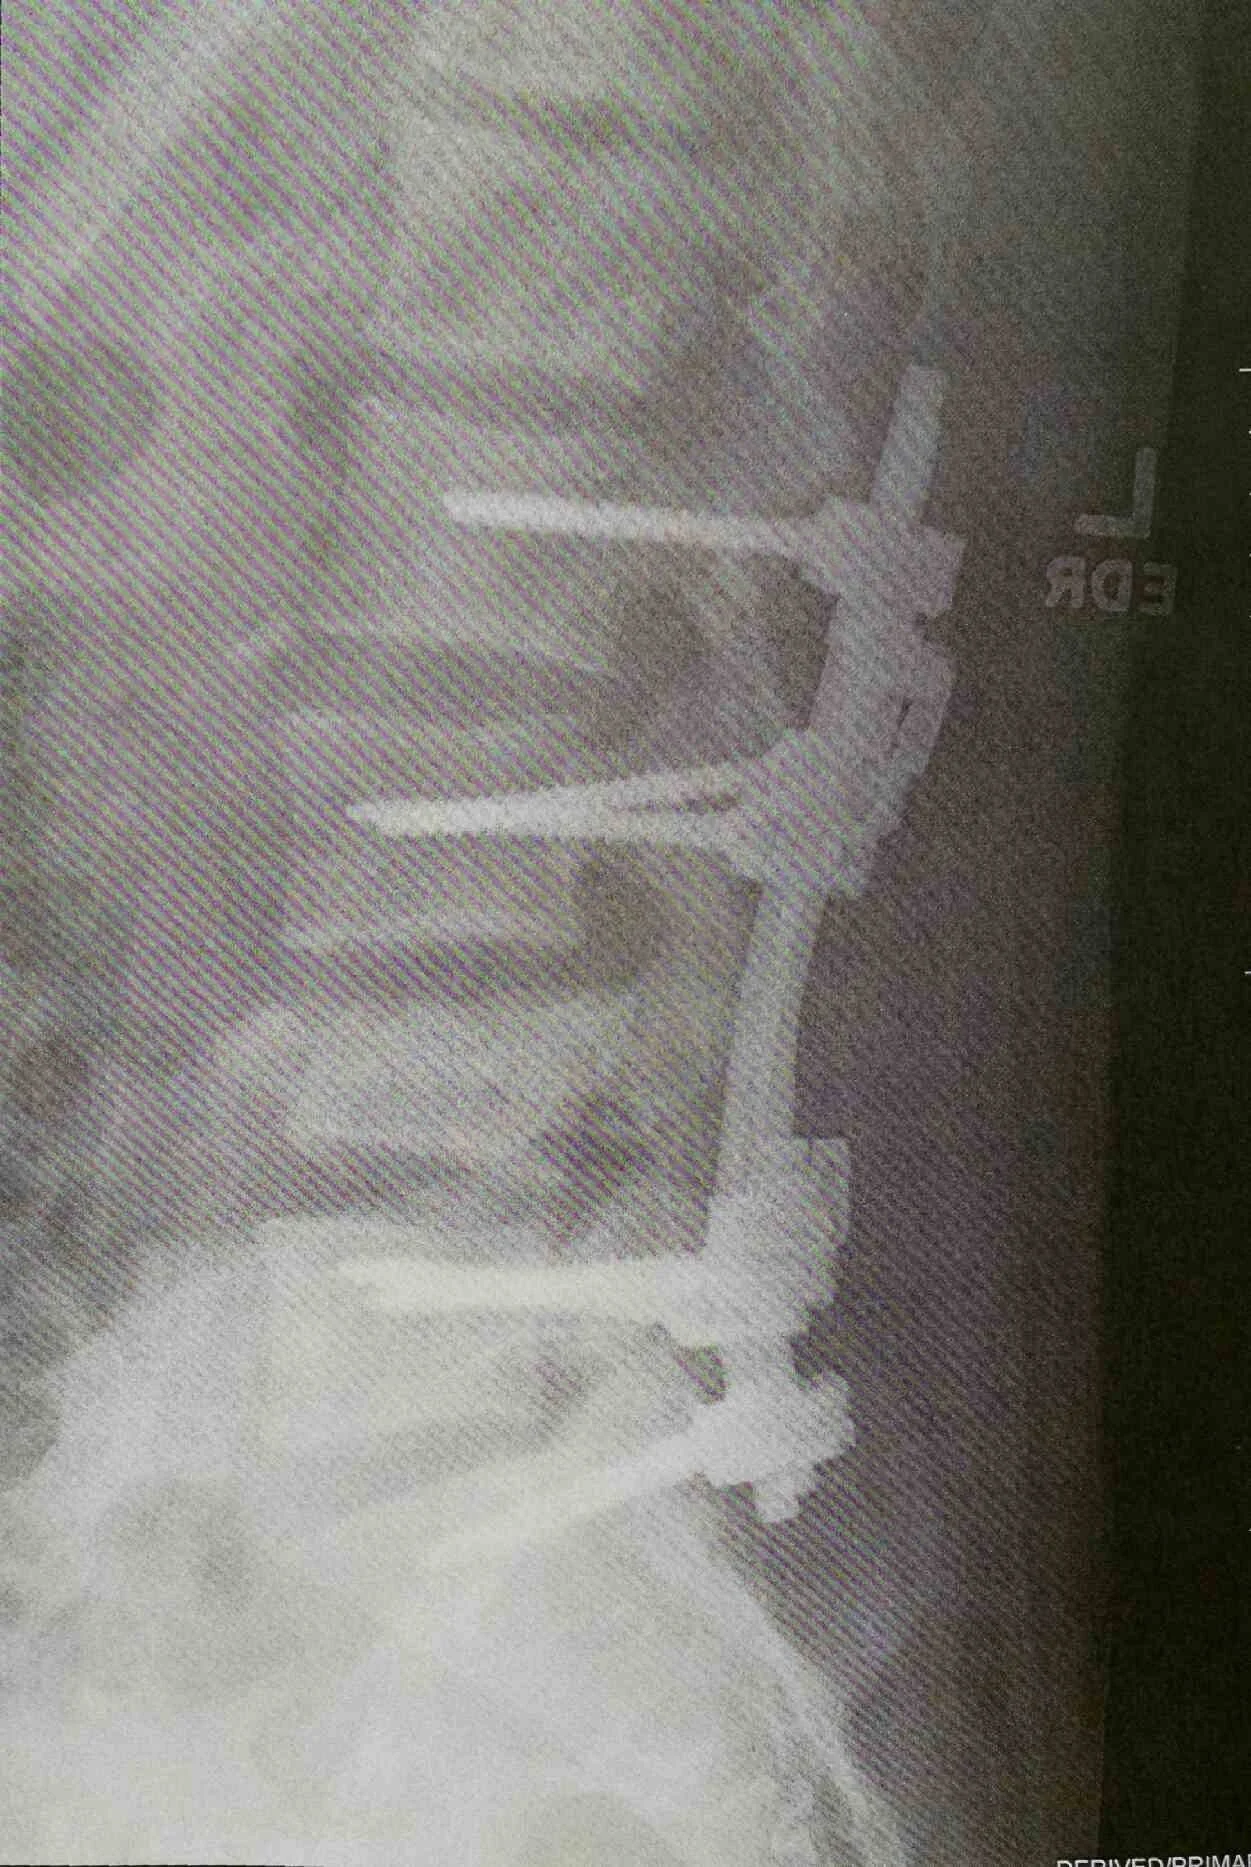

At 15, Heath broke his back, an L4 burst fracture, that nearly left him paralyzed—an experience that exposed him to the harsh realities of our broken healthcare system and sparked his passion for advocacy. Since then, he has undergone two major surgeries and continues to live with chronic back pain. These challenges have shaped his perspective and made him a strong voice for the disability community in Concord. With disability representation still lacking in government—and with Republicans in Washington repeatedly targeting critical programs—Heath believes we need leaders who will stand up for Medicare, Medicaid, and Social Security, and ensure no one is denied the care they need.